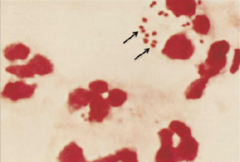

Haemoglobin

Haemoglobinuria (Split red blood cells)